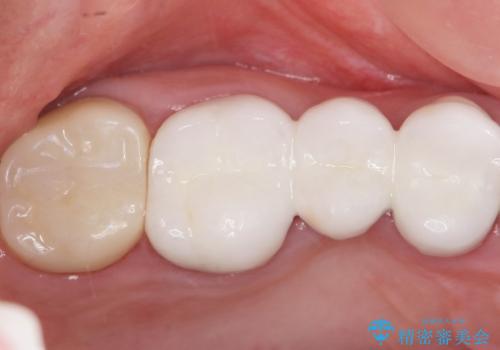

患者様のご希望により、金属を使わないオールセラミックのブリッジによる補綴治療を行いました。

金属の土台も除去し、ファイバーコア(金属を使わない強度のあるしなやかな土台)へやりかえました。

自然な仕上がりと咬み心地に喜んで頂けました。

クラウンの種類:オールセラミッククラウン スタンダード